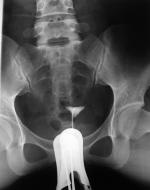

上述方法中,X線子宮輸卵管碘油造影和腹腔鏡準確性高,是確診輸卵管阻塞的可靠手段,子宮輸卵管碘油造影較腹腔鏡無創傷、費用低等特點。子宮輸卵管碘油造影更是國際衛生組織力薦使用的診斷方法。

(3)若套用金屬導管將造影劑充滿導管,排盡空氣,而後將導管插入子宮頸,堵緊宮頸外口,不至使造影劑外溢,在X線透視下觀察造影劑流經宮腔及輸卵管情況並攝片。①在這個時期最好要攝片兩張,第一張掌握在造影劑充滿子宮及輸卵管全程的時候,造影劑經輸卵管進入盆腔內一少部分時攝第二張,如造影劑進入盆腔內彌散過多拍第二張,由於造影劑進入盆腔內彌散將影響對輸卵管具體情況的準確觀察,而後再次注入一定量的造影劑,順便拔出導管後讓患者適當走動,24小時左右待造影劑在盆腔內充分彌散時拍最後一張延遲造影片。②使用歐乃派克造影劑,在手術當中可進行拍攝,無需24小時後再行X線拍片。若套用氣囊導管進行造影其過程和金屬導管造影過程大體相同。須要注意的是在進行子宮輸卵管碘油造影檢查過程的拍片的抓拍時機,一定要掌握在造影劑流經輸卵管,保持一定壓力在造影劑流動的過程中拍片,只有這樣才能清楚的了解管腔的具體通暢情況。

最佳檢查時期為月經後5~10d,造影劑有碘化油、76%泛影葡胺等。造影劑劑量一般為10ml,或更多(觀察輸卵管充分造影為宜)也與患者耐受程度有關。